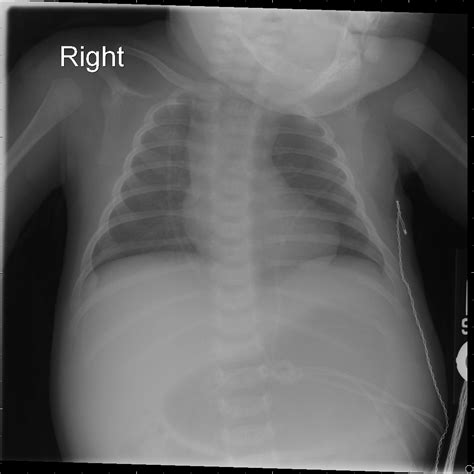

A boot shaped heart is a rare congenital heart defect where the heart takes on an unusual shape, resembling a boot. This condition is often associated with other cardiac abnormalities and can significantly impact an individual's health and quality of life. Understanding the anatomy and physiology of a boot shaped heart is crucial for medical professionals and patients alike.

The heart is a complex organ responsible for pumping blood throughout the body. In a boot shaped heart, the chambers and valves may be malformed or misaligned, leading to various complications. The most common issues include:

• Ventricular Septal Defect (VSD): A hole in the wall separating the heart's lower chambers.

• Atrial Septal Defect (ASD): A hole in the wall separating the heart's upper chambers.

• Pulmonary Stenosis: Narrowing of the pulmonary valve, which controls blood flow from the heart to the lungs.

• Aortic Stenosis: Narrowing of the aortic valve, which controls blood flow from the heart to the rest of the body.

These defects can cause blood to flow inefficiently, leading to symptoms such as shortness of breath, fatigue, and cyanosis (a bluish discoloration of the skin due to lack of oxygen).